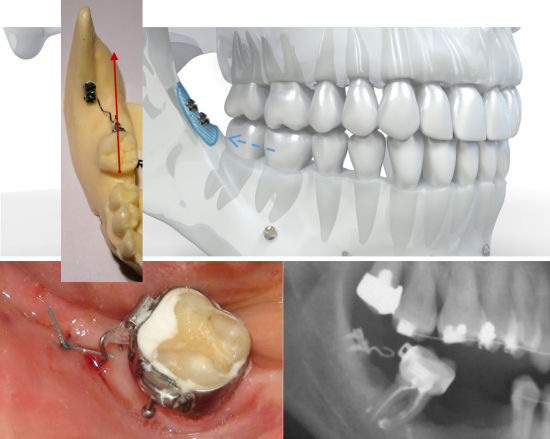

Système CT8 - Mésialisation molaire inférieure

La mésialisation molaire peut être exécutée grâce au Kit Mésialisation molaire mandibulaire pour une action unilatérale avec le CT8-1. Elle peut également être exécutée grâce au Kit Mésialisation molaire mandibulaire bilatérale pour une traction exercée des deux côtés par le CT8 tunnel.